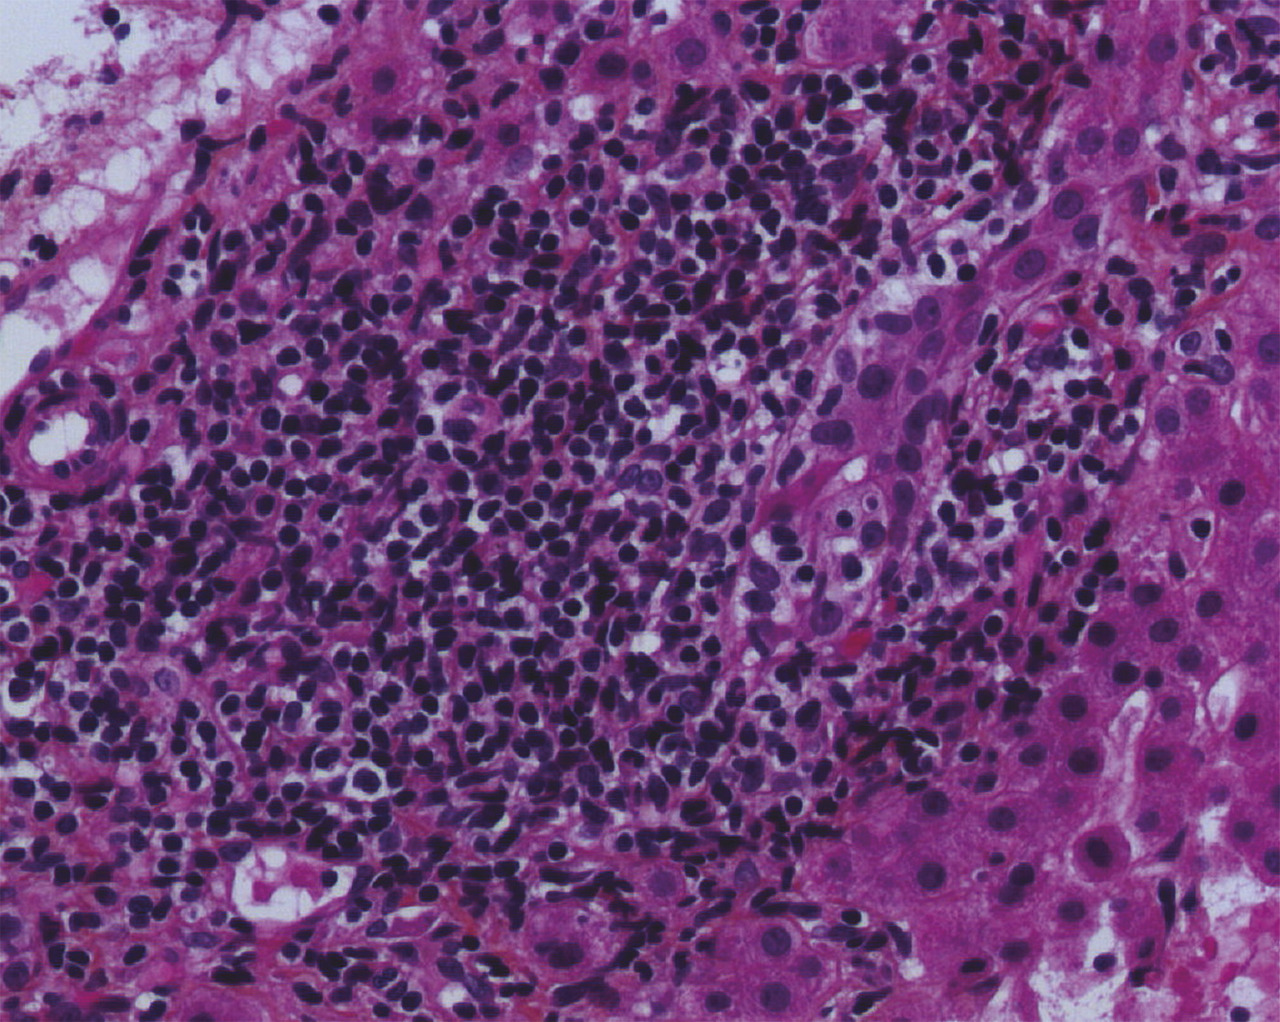

Biologiquement, il existe une cholestase chronique, définie par une augmentation concomitante des phosphatases alcalines (PAL) et de la gammaglutamyl transpeptidase (GGT) depuis au moins 6 mois. La cholestase peut être isolée, ou associée à une élévation modérée des transaminases et, plus rarement, à un ictère, qui est un signe de sévérité. Une augmentation des immunoglobulines sériques de type M (IgM) est fréquente. Le marqueur le plus spécifique de la CBP est la présence d’anticorps anti-mitochondrie de type M2 (AAM-2), à un taux sérique supérieur ou égal à 1/40e, présents chez plus de 95 % des patients atteints de CBP. Quand la biopsie hépatique est réalisée, on peut parfois observer des lésions de cholangite destructrice lymphocytaire ou granulomateuse, associées à un infiltrat portal et périportal lympho-plasmocytaire, éventuellement organisé en granulome, et parfois à une ductopénie (perte des canaux biliaires dans plus de 50 % des espaces portes) et à une fibrose (fig. 1 ).

Biologiquement, il existe une cholestase chronique, définie par une augmentation concomitante des phosphatases alcalines (PAL) et de la gammaglutamyl transpeptidase (GGT) depuis au moins 6 mois. La cholestase peut être isolée, ou associée à une élévation modérée des transaminases et, plus rarement, à un ictère, qui est un signe de sévérité. Une augmentation des immunoglobulines sériques de type M (IgM) est fréquente. Le marqueur le plus spécifique de la CBP est la présence d’anticorps anti-mitochondrie de type M2 (AAM-2), à un taux sérique supérieur ou égal à 1/40e, présents chez plus de 95 % des patients atteints de CBP. Quand la biopsie hépatique est réalisée, on peut parfois observer des lésions de cholangite destructrice lymphocytaire ou granulomateuse, associées à un infiltrat portal et périportal lympho-plasmocytaire, éventuellement organisé en granulome, et parfois à une ductopénie (perte des canaux biliaires dans plus de 50 % des espaces portes) et à une fibrose (